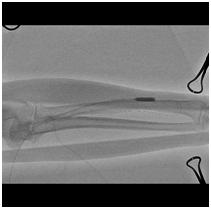

橈骨骨折

CTとはコンピュータ断層撮影(computed tomography)の略で、人体の360度方向からX線を照射して画像を得る装置です。検査時間は5分から15分(1回の撮影時間は10秒ほど)と比較的短くよく用いられる画像検査のひとつで、あらゆる領域における疾患のスクリーニングから精査目的の検査まで、画像診断の中心的な役割を果たしています。

検査内容によっては造影剤という薬を注射して検査を行う場合があります。